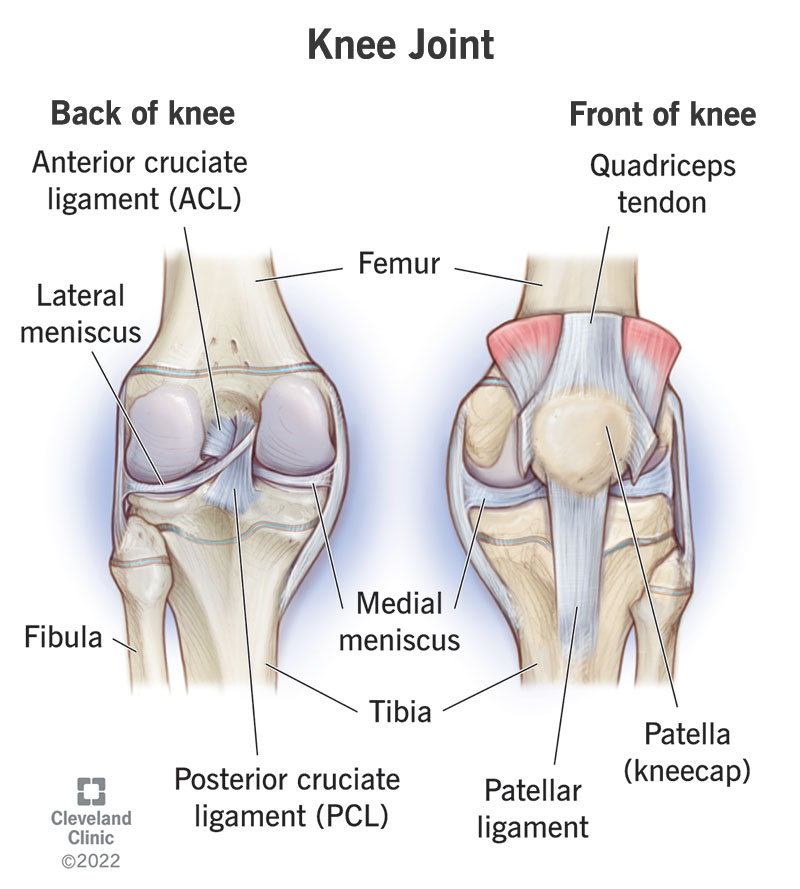

Image-2 – PCL

2 PCL (Posterior Cruciate Ligament)

What is PCL?

The Posterior Cruciate Ligament is located behind the ACL and is stronger. It connects the femur to the tibia and controls backward movement of the tibia relative to the femur.

Function

- Prevents tibia from moving backwards excessively

- Stabilizes knee especially during downhill walking, kneeling and bending